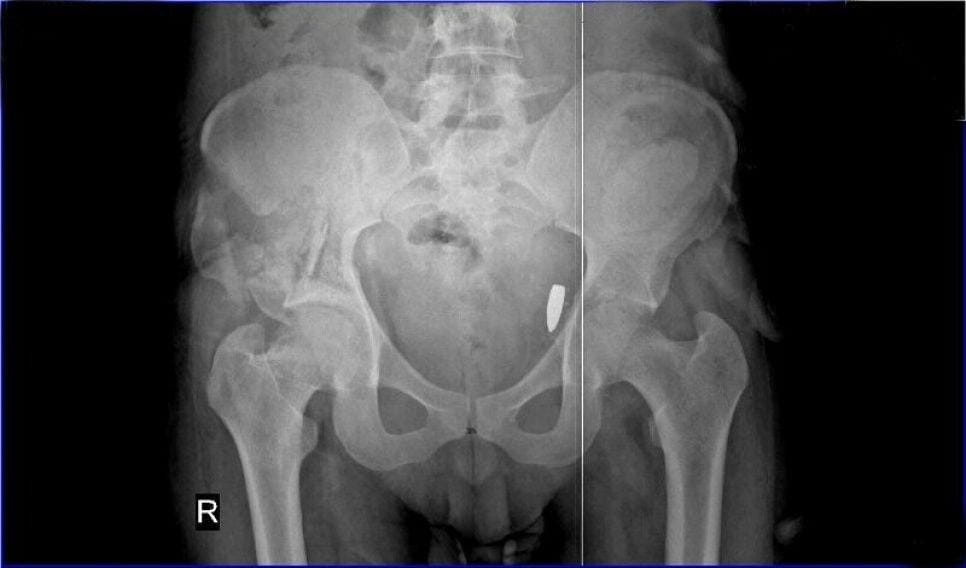

Sekitar 90 persen kematian orang yang tertembak akibat kehilangan darah. Kamu bisa mengalami pendarahan hebat jika peluru mengenai arteri brakialis di lengan, satu arteri inguinal bilateral di pangkal paha, atau arteri subklavia di bawah tulang selangka.